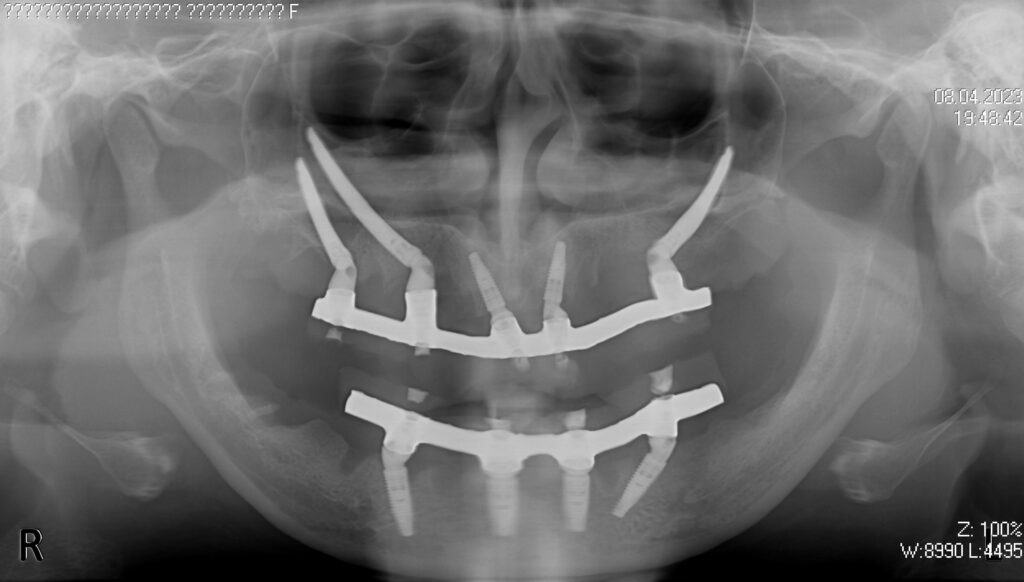

На верхней и нижней челюстях были удалены зубы, которые находились в неудовлетворительном состоянии, проведена комплексная имплантация,

на нижней челюсти установлены 4 классических имплантата NeoDent, на верхней — 2 классических и 3 скуловых имплантата NeoDent.

Спустя 6 дней на обеих челюстях зафиксированы металлоакриловые протезы.

снимок